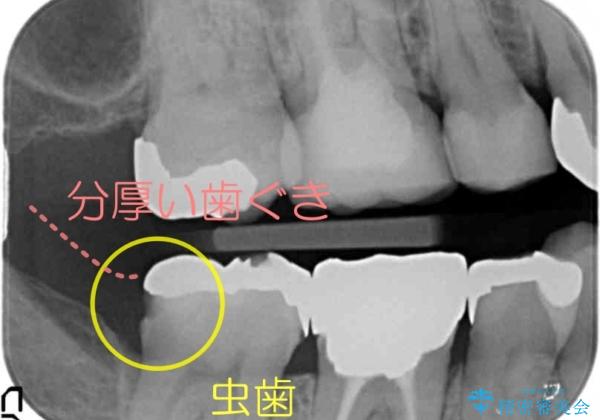

- 右下奥の銀歯の下が虫歯になっていました。

歯ぐきの下までしっかり修復するために、歯周外科手術を含めた治療を行いました。

歯ぐきの中まで虫歯の場合は、まず、虫歯も取りきることが難しいです。

また、被せ物のきわを歯ぐき深くに設定してしまうことになり、正確な歯型がそのままでは取れません。また、歯ぐきのみを取り除いても一時的な処置となり、また歯ぐきが再生してしまうため、最終的には歯ぐきの腫れが治りません。

今回は、歯周外科手術を行い、歯ぐきの厚みを薄くし、また、歯槽骨の高さも整えて、歯周環境を整えました。